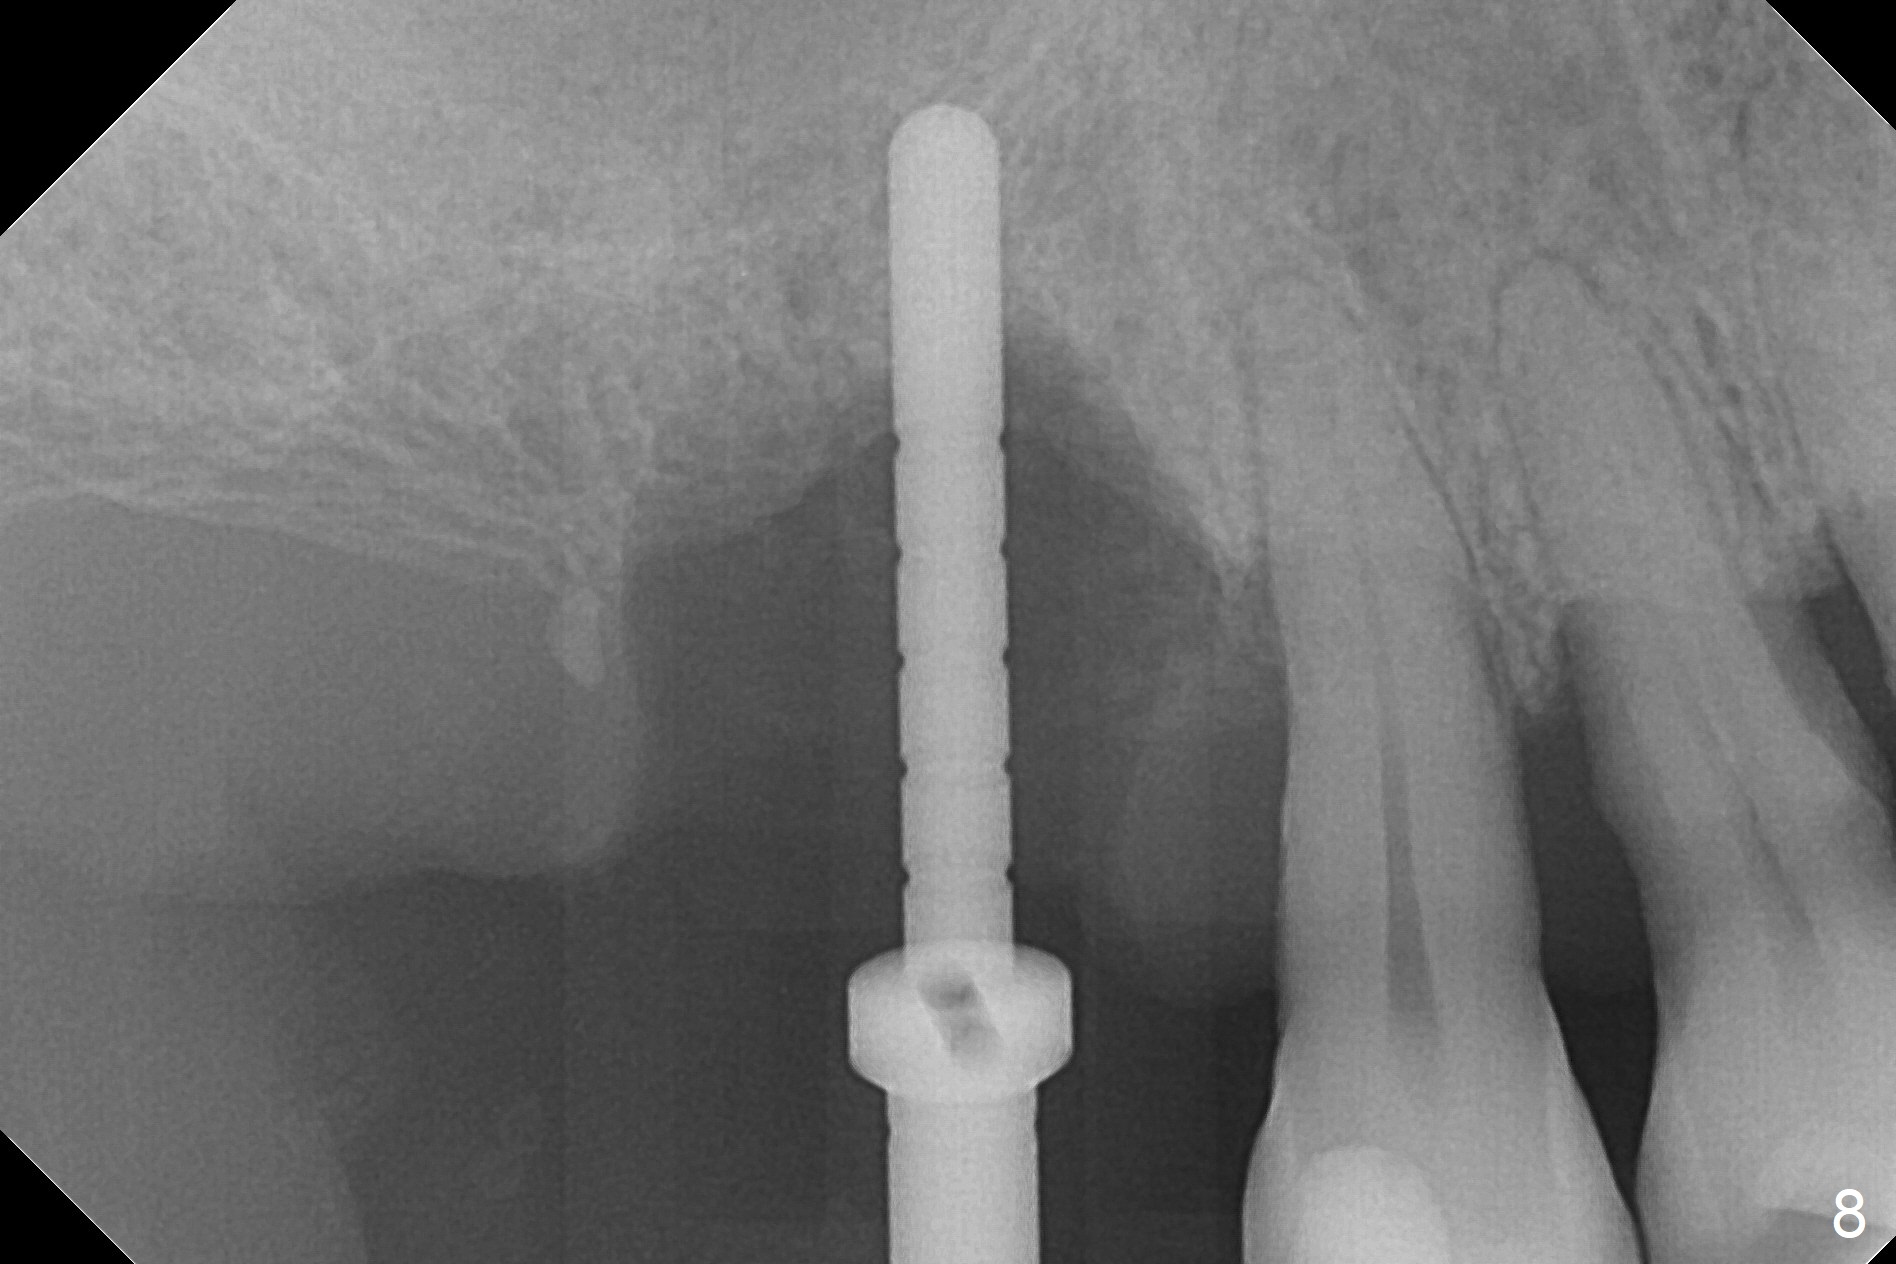

After extraction of the tooth #3 (Fig.1,2), the palatal socket (P) is as wide as the buccal one (B; Fig.3,4 (socket impression)), as compared to the roots), suggesting bone loss is more severe palatally than buccally. There is a circular area in the buccal slope of the palatal socket, in which the bone looks thin (purplish: presumably the sinus membrane underneath, Fig.5,7 (blue circle)). It appears that the palatal slope of the buccal socket (Fig.6, 7 red dashed line) is the most appropriate site for osteotomy (Fig.8). Prior to inserting 5.3 mm tap drill (Fig.9), the mesiopalatal region of the osteotomy (corresponding to the blue circle in Fig.7) perforates without sinus membrane tear. A small piece of Osteogen plug is placed in the perforation before inserting a 5.3x10 mm SM implant (Fig.10,11). Following placement of another piece of Osteogen plug in the palatal socket and of a 4.8x7(6) mm abutment, mineralized cortical and cancellous bone is placed (*). Collagen plug and an immediate provisional are used to close the socket opening. CT taken 11 months post cementation shows that the implant is placed within bony boundary, although buccally (Fig.12 B). Bone graft seems to heal in the sinus (Fig.13 (sagittal section),14 (coronal section) white * (Osteogen plug) and in the socket (brown * (allograft and Osteogen)).